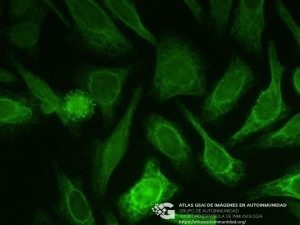

- Nombre de la imagen:anticuerpos anti-Vimentina

- Nombre en inglés:Vimentin antibodies

- Tecnología empleada:Inmunofluorescencia indirecta

- Sustrato:Células HEp2

- Patrones HEp-2 Grupos:Citoplasmático (AC-12 a AC-23)

- Patrón (Nomenclatura estandarizada):AC-16 - Citoplasmático fibrilar filamentar

- Clínica del paciente:Fibrosis Pulmonar Idiopática